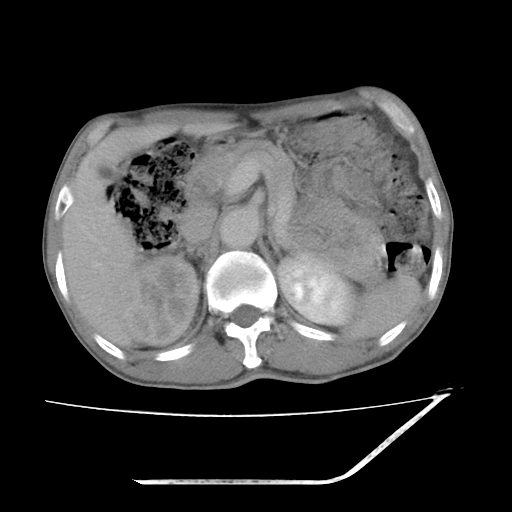

增强

考虑右肾盂癌,肾动脉受侵,右肾功能减退,右肾盂输尿管积水,管壁增厚,考虑种植转移,应该把下面扫完的

支持右侧肾盂癌伴肾静脉瘤栓形成可能性大,右肾结石.肝右叶后段低密度影,不除外转移.

右肾盂旁ca并肾静脉瘤栓形成/肾功能降低。

右肾结石。

右肾盂癌,肾动脉受侵,右肾盂输尿管积水,管壁增厚,考虑种植转移

支持 右侧肾盂癌伴肾静脉瘤栓形成可能性大,右肾结石;肝右叶后段低密度影,不除外转移。

1.右侧肾盂癌伴肾盂积水。

2.肾脏功能减退,原因有:(1)肾动脉受侵。(2)肾静脉受侵(3)肾积水,等。本例,肾动脉显影较好,但受压明显;肾静脉无明显显示,受压或静脉癌栓,下腔静脉腔内未见明显充盈缺损。

3.右侧上段输尿管扩张,原因:(1)积水所致;(2)种植。